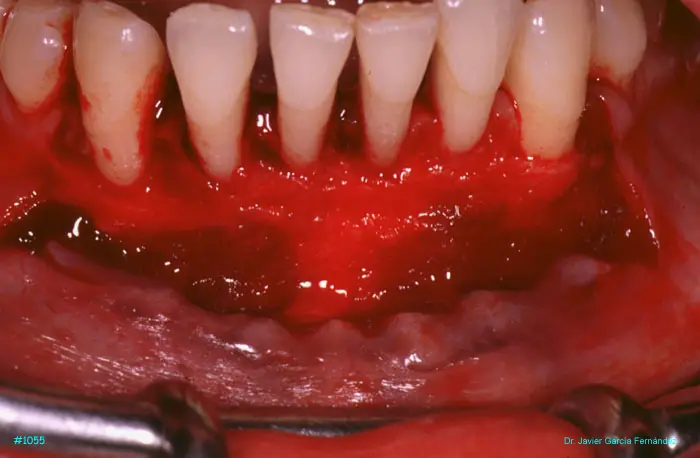

Atlas of Surgical Techniques in Periodontics. Chapter III. Atlas de Técnicas Quirúrgicas en Periodoncia